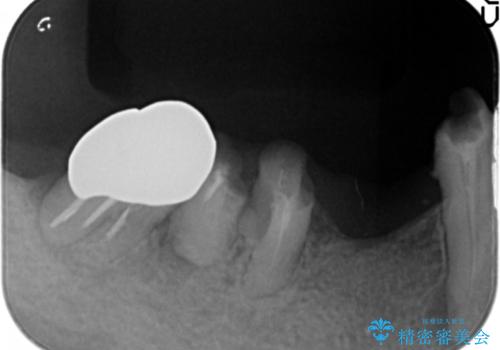

精査したところ、右下4の根尖病変及び右下5の欠損を認め、右下6は残根となり保存不可能な状態でした。

保存不可能な歯を抜去後、インプラント治療と根管治療を行いました。

- ¥1,177,000 (根管治療、土台、骨増生、インプラント・アバットメント×2本、仮歯・クラウン×3本) ※税込費用は治療当時の料金となります